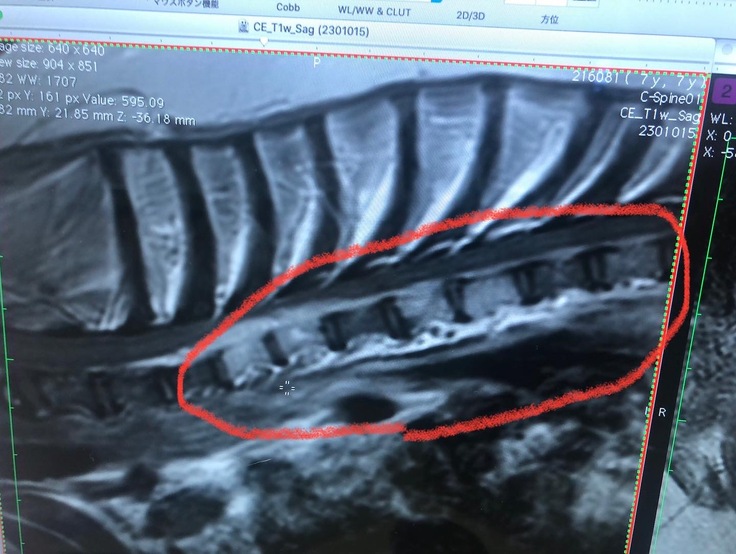

C6の滲んで見えるのが腫瘍です かなり大きいです

岐阜大学動物病院にて、頚椎に出来た、腫瘍を小さくする為に

放射線治療にて対応して頂きました。

※画像 下段左から3目の骨が腫瘍により、融解そして変形

この変形がラッキ-を苦しめています。